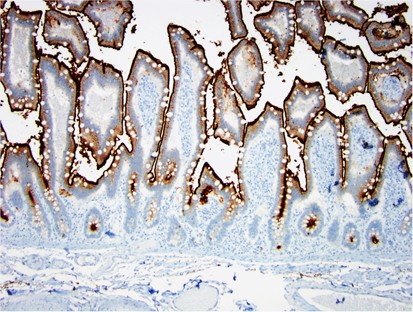

Normal enteric brush border staining with CD10. Note contiguous, strong positivity of the luminal surface of the epithelium.